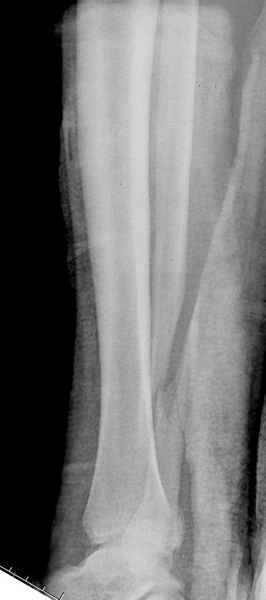

При реконструкции голеностопа, о важности восстановления длины малоберцовой для профилактики пост травматического артроза разбирали в предыдущих дискуссиях. Нарушенную биомеханику голеностопа без восстановления длины малоберцовой, не восстановить только швом медиальной связки.

Расширенная медиальная щель более чем на 4 мм и укорочение малоберцовой более чем 2 мм, а перелом заднего края большеберцовой смещения более 2мм с вовлечением 30% поверхности сустава, считается отходом от нормы голеностопного сустава, и подлежит к оперативному вмещательству.

Здесь похожий случай трехнедельной давности, перелом почти сросся и была укорочена малоберцовая, на операции длину малоберцовой смогли восстановить только после того, когда проксимальнее пластины ввели шуруп и использовали его как толкатель, с помощбю дистракционого инструмента (lamina spreader).